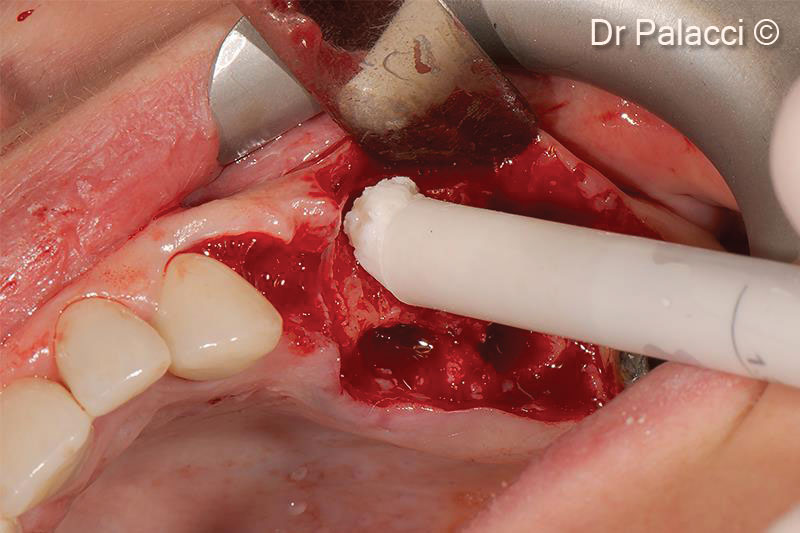

Răng bị nhổ, toàn bộ xương môi bị mất có thể thấy rõ sự tiêu xương nghiêm trọng

GTO được cấy ghép vào các ổ răng

Một màng collagen bao phủ vùng khuyết tật được lấp đầy bằng vật liệu sinh học